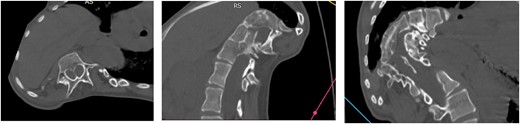

Computed tomography (CT) visualizes diastematomyelia in the form of a calcar at the level of Th11, Th12, L1 vertebrae (Fig. 4).